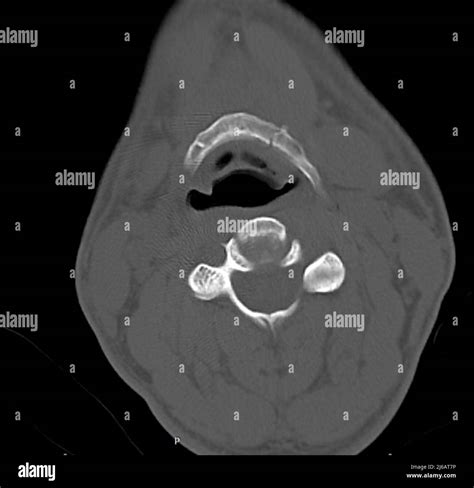

Understanding the intricacies of the hyoid bone and its significance in medical diagnostics, particularly through imaging techniques like the Hyoid Bone Coronal CT, is crucial for healthcare professionals. The hyoid bone, a small U-shaped bone located in the neck, plays a vital role in various physiological functions, including swallowing, speaking, and breathing. This blog post delves into the anatomy, clinical relevance, and diagnostic procedures involving the hyoid bone, with a focus on the Hyoid Bone Coronal CT scan.

The hyoid bone is a unique structure in the human body as it is the only bone that does not articulate directly with any other bone. It is suspended by muscles and ligaments in the neck and serves as an attachment point for several muscles involved in tongue movement, swallowing, and speech. The hyoid bone consists of three main parts:

• Body: The central part of the hyoid bone.

• Greater Cornua: The larger, posteriorly directed horns.

• Lesser Cornua: The smaller, anteriorly directed horns.

This complex structure allows the hyoid bone to act as a fulcrum for the muscles of the tongue and larynx, facilitating essential functions like swallowing and phonation.

Imaging techniques play a pivotal role in the diagnosis and management of hyoid bone-related conditions. Among these, the Hyoid Bone Coronal CT scan is particularly valuable. This imaging modality provides detailed cross-sectional views of the hyoid bone and surrounding structures, aiding in the accurate diagnosis of various pathologies.

Interpreting a Hyoid Bone Coronal CT scan requires a thorough understanding of the normal anatomy and potential pathological findings. Key points to consider include:

• Bone Structure: Assess the integrity of the hyoid bone, looking for fractures, erosions, or other abnormalities.